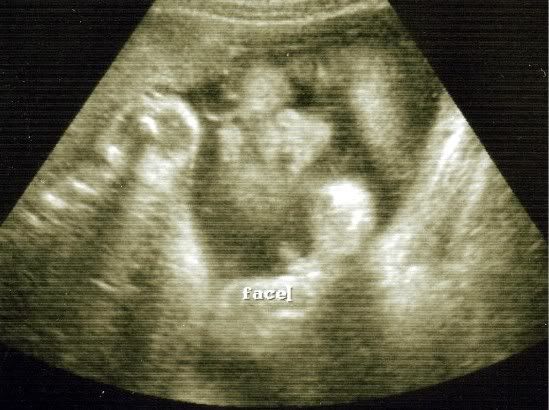

They did another U/S today so here are Braedin's latest pictures.

#1 I love this one so much you can see his sweet little face so well in it.